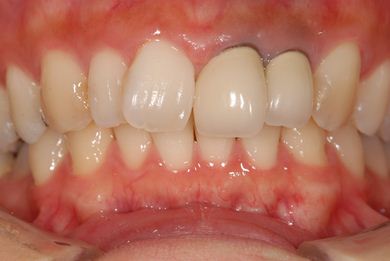

| 性別/年齢 | 女性 / 31歳 | ||||||||||||||||||||||||||||||||

| 主訴 | 前歯の歯茎が黒ずんでいるので、改善したい。 | ||||||||||||||||||||||||||||||||

| 治療方針 | 上顎前歯、メタルボンドセラミッククラウンからオールセラミッククラウンにする事で、審美的回復を行う。 | ||||||||||||||||||||||||||||||||

| 治療内容 | CAD/CAMオールセラミッククラウン2本(セラミック用土台2本) | ||||||||||||||||||||||||||||||||

| 総治療費 | 142,800円 | ||||||||||||||||||||||||||||||||

| 治療期間 | 2ヶ月 |